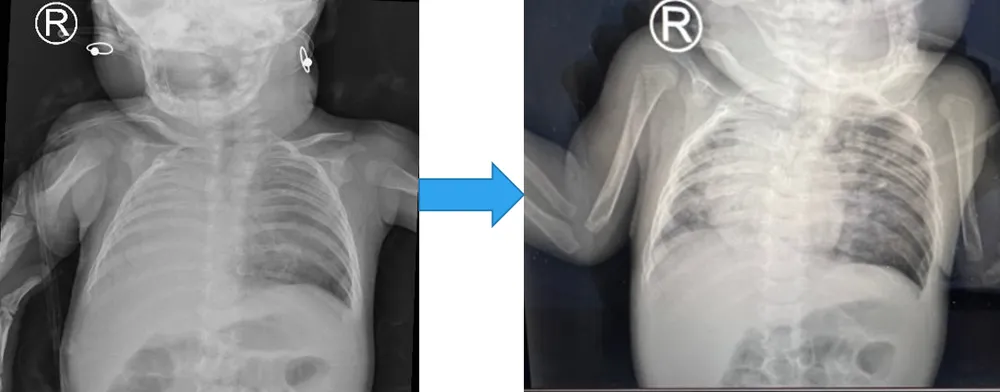

Trước phẫu thuật, phổi phải xẹp (ảnh Xquang bên trái) và nở dần sau khi được phẫu thuật.

Sau khi dùng kháng sinh tích cực để ổn định tình trạng nhiễm trùng, ê kíp lên chương trình mổ. Trẻ được phẫu thuật cắt - nối phế quản gốc phải vào khí quản, khâu bít lỗ thông thực quản nơi phế quản phải cắm vào trước đó. Sau hơn 1 tuần điều trị tích cực, phổi phải mới nở ra. Bệnh nhi được cai máy sau gần 1 tháng, tự thở khí trời.